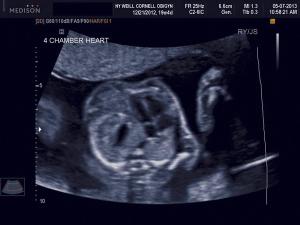

Ultrasound imaging is a key prenatal tool for revealing structural anomalies that may point to genetic conditions. This slideshow is Part 1 of our collection of ultrasound anomalies and includes first-trimester anomalies and second-trimester anomalies of the head and brain. Part 2 will discuss second-trimester anomalies of the body and limbs.